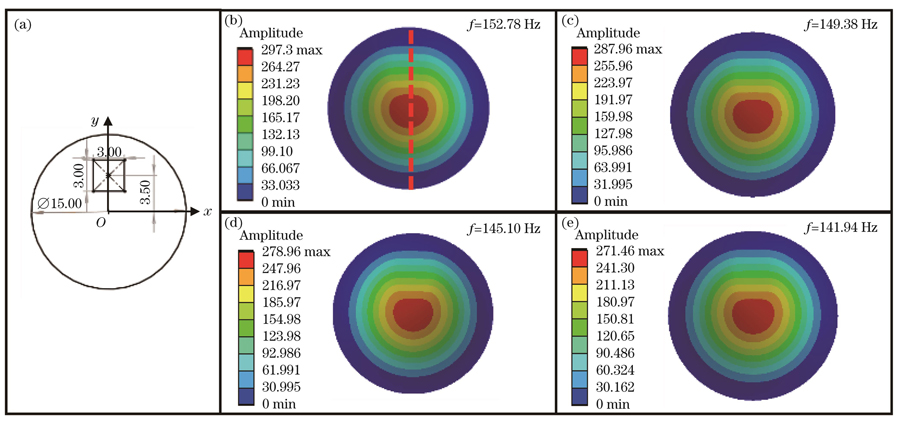

耳膜钙化常常是由耳部炎症引起的,表现为耳膜表面白色斑块状钙盐沉积,钙化严重的情况下会导致听力下降。如

图 7. 钙化薄膜一阶振动模态的仿真结果。(a)钙化薄膜示意图;(b)~(e)钙化厚度为0.1、0.2、0.3、0.4 mm的薄膜

Fig. 7. Simulation results of first-order vibration modes of calcified films. (a) Schematic of calcified film; (b)-(e) films with calcification thickness of 0.1, 0.2, 0.3 and 0.4 mm, respectively

在钙化薄膜的实验验证中,为了模拟真实的耳膜钙化情况,在薄膜表面涂抹不同厚度的尺寸为3 mm×3 mm的钙化材料。分别在相同位置处涂抹0.1 mm和0.3 mm厚度的钙化材料,如

图 13. 钙化薄膜的一阶振动模态图。(a)钙化厚度为0.1 mm的薄膜;(b)钙化厚度为0.3 mm的薄膜

Fig. 13. First-order vibrational mode diagrams of calcified films. (a) Film with calcification thickness of 0.1 mm; (b) film with calcification thickness of 0.3 mm